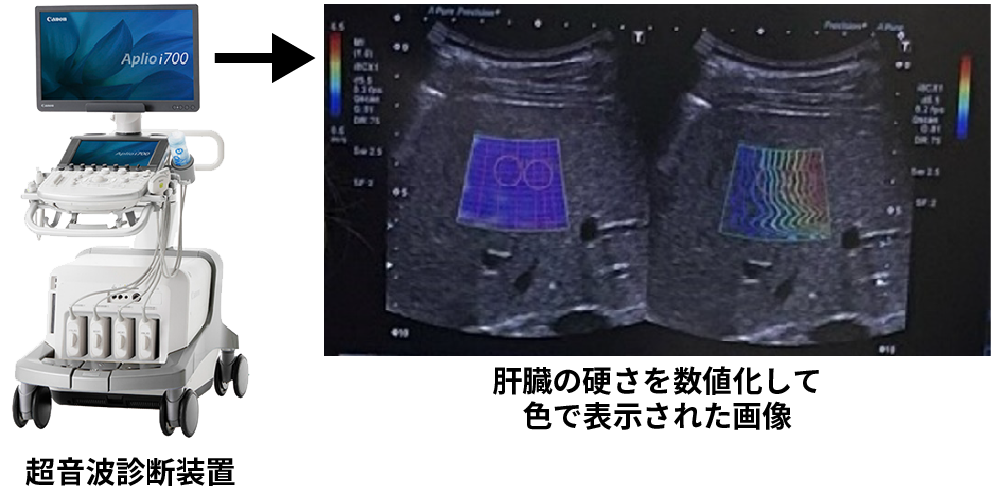

肝硬変の検査「超音波エラストグラフィー」

しかし、近年では超音波によって肝線維化の進行度や広がりなどを画像で確認する「超音波エラストグラフィー」が行われるようになりました。

この検査は、身体に針を刺さずに実施できることから、患者さんにとって負担が少なく診断できる検査方法です。

当院では、2024年1月に導入し、これまでウイルス性肝炎、脂肪性肝障害などの疾患をもつ患者さんに実施しています。